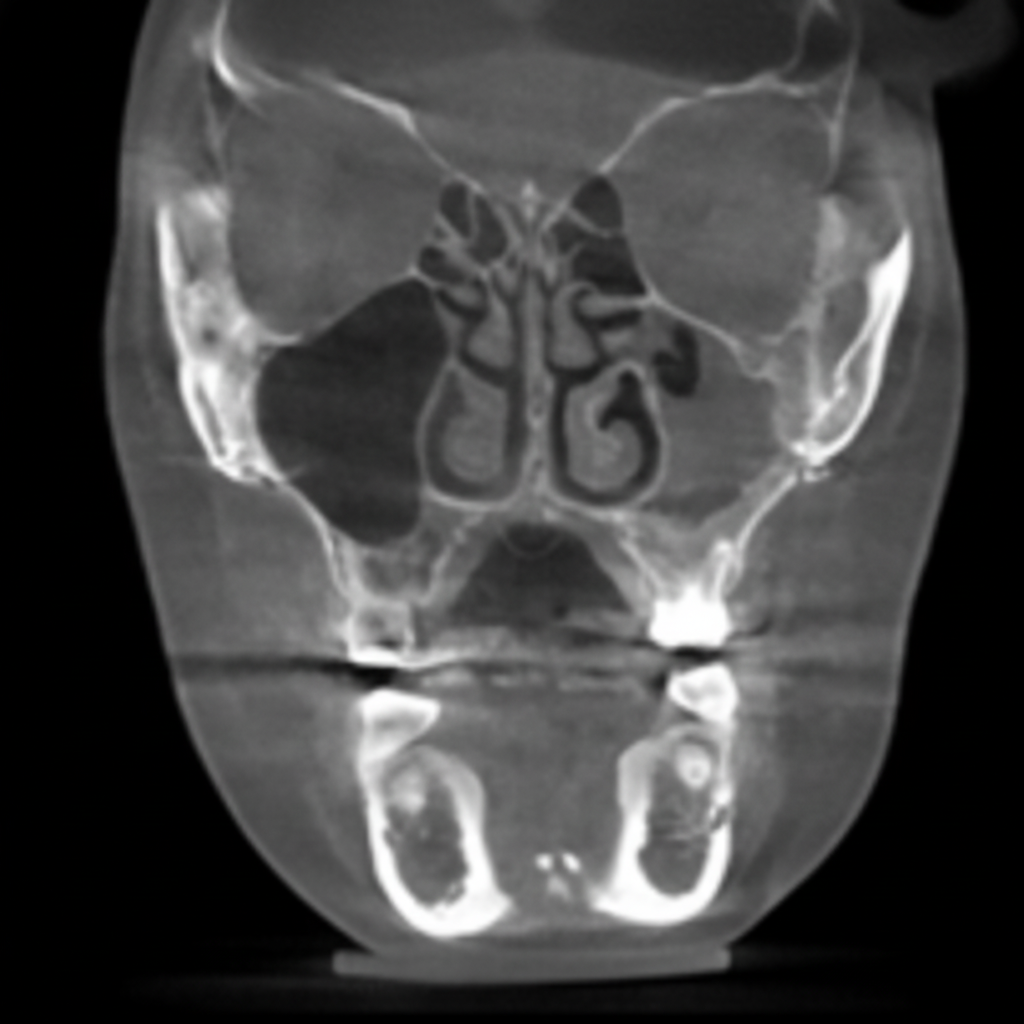

02 VIBE 수술 전 정밀진단

02

3D CT 분석에 의한 정밀진단

3D CT 분석을 통해 코뼈, 비중격, 연골길이, 내부변형 등 코 내부 상태에 대한 정확한 파악이 가능합니다.

코재수술의 경우 보형물의 위치, 고개기 대한 파악, 코골 연골과 변형 정도에 대한 예측을도 오차

다음 안정적인 결과를 도출합니다.

CT사진 1

CT사진 2

3D-CT 정밀진단

3D-CT

정밀진단

겉으로 보이지 않는

코 뼈, 비중격 연골,

비대칭 유무 확인